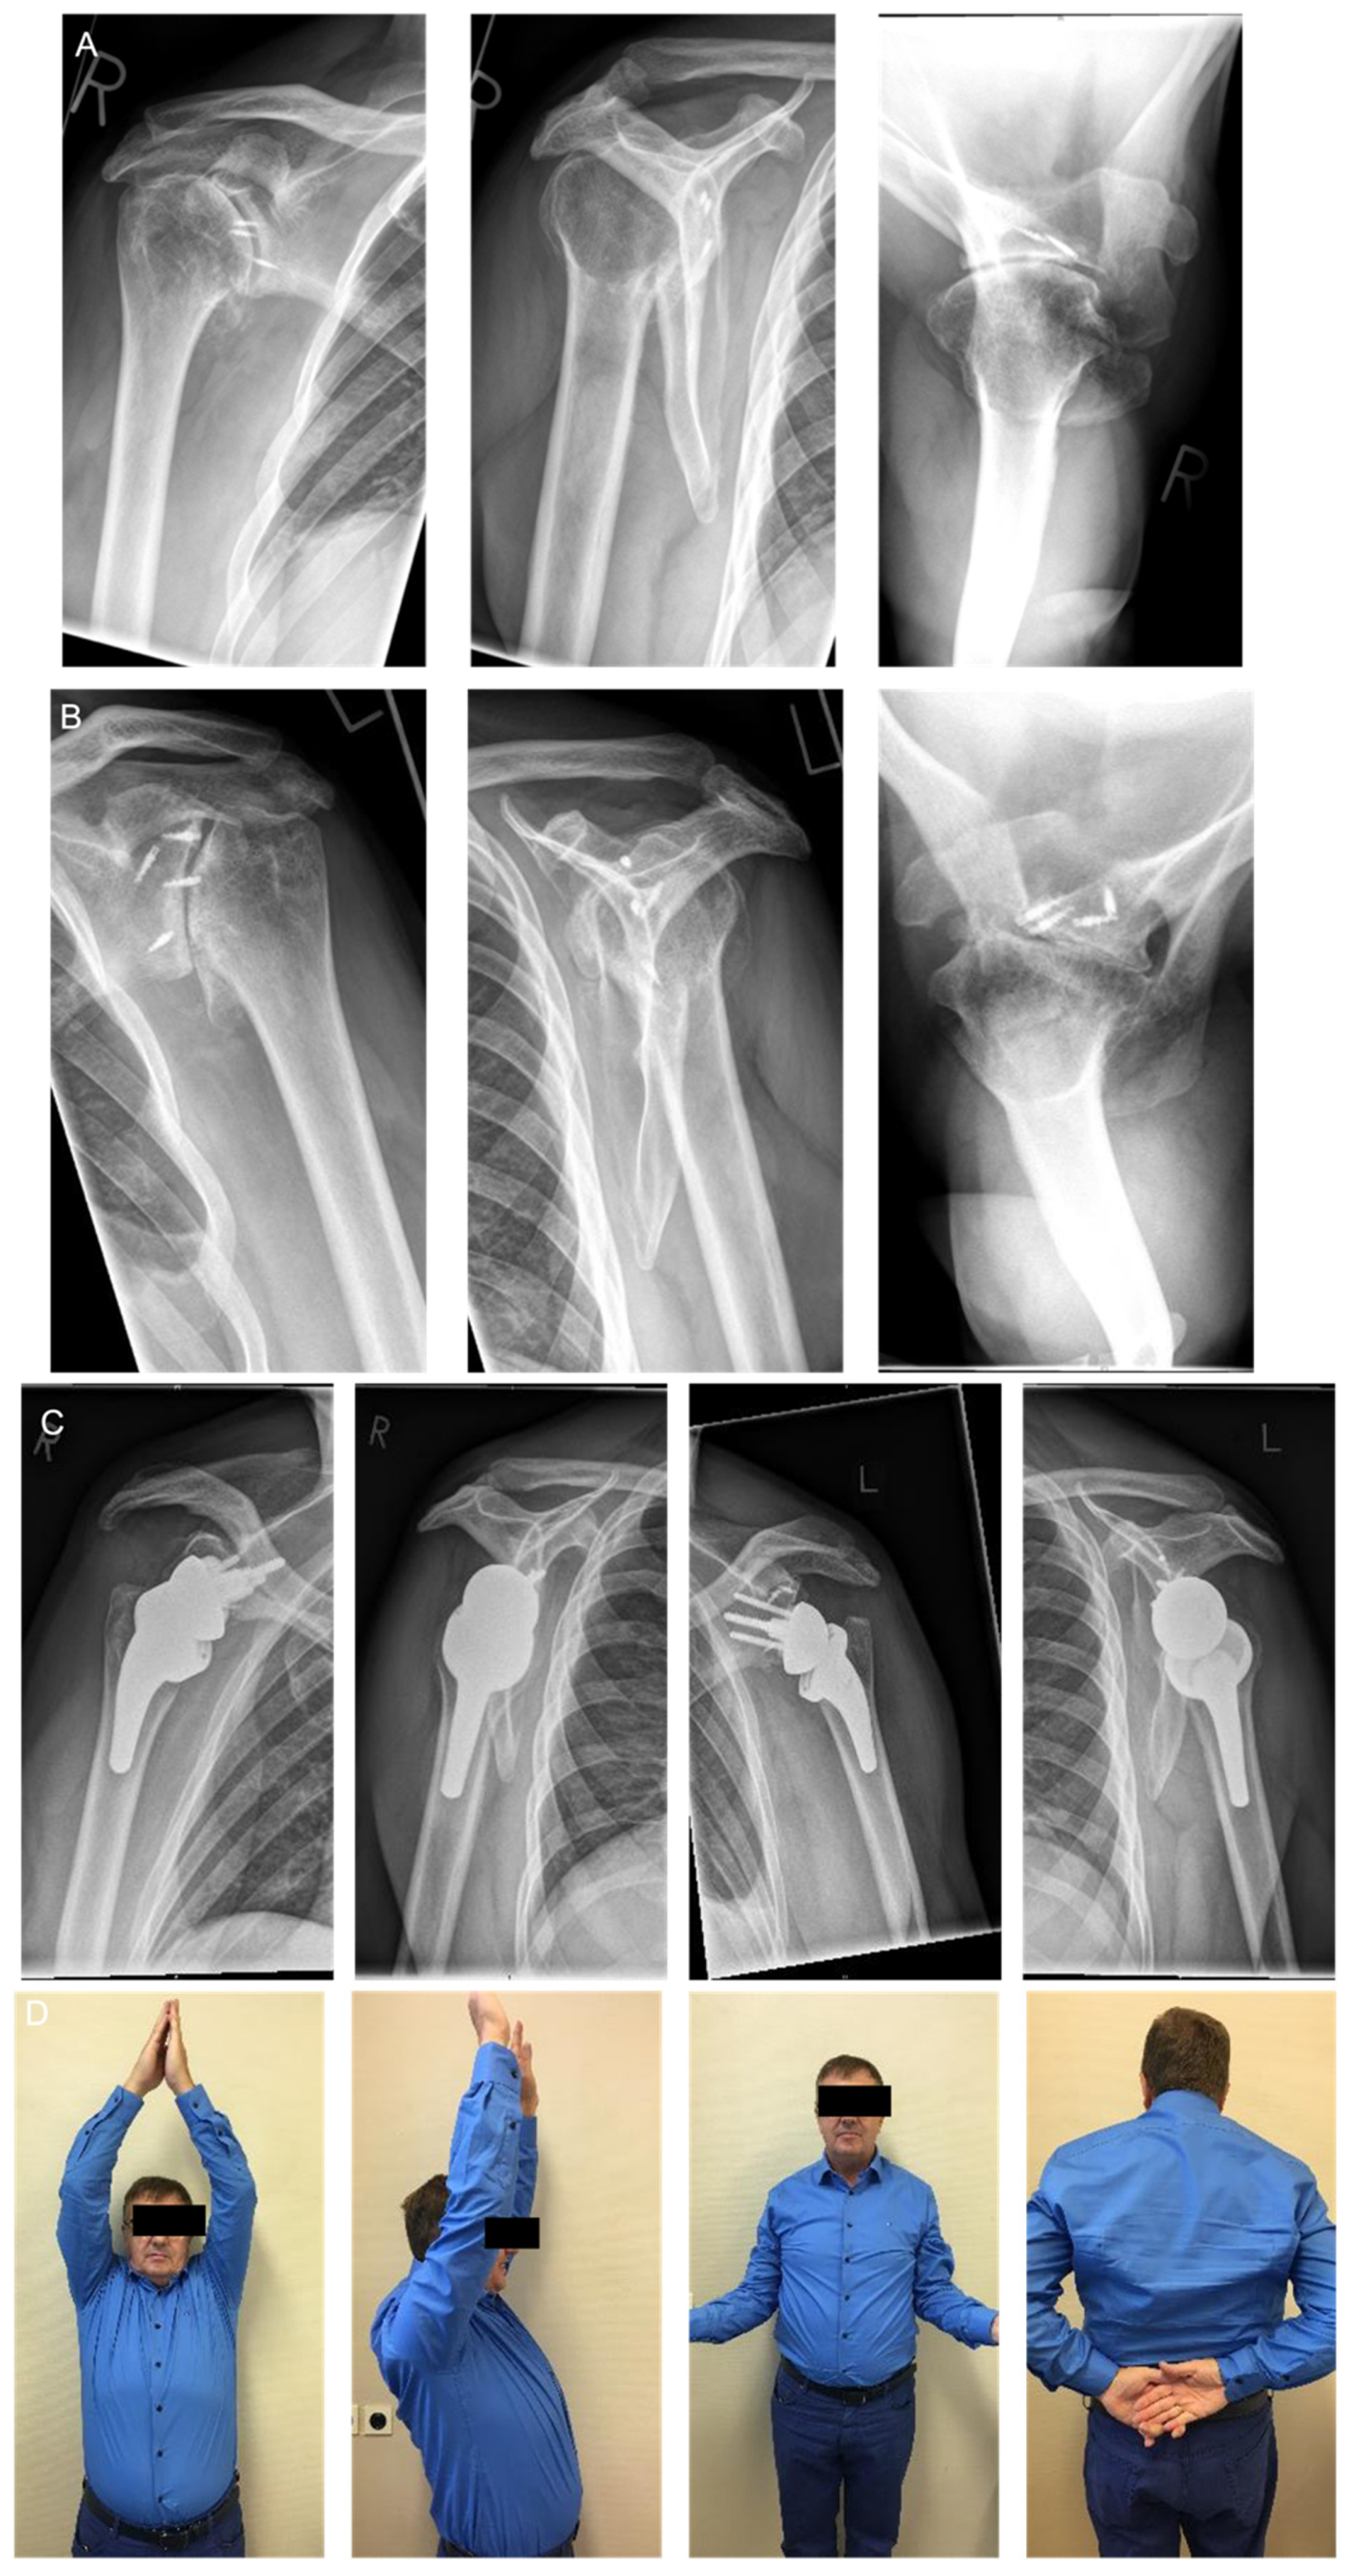

6.4. Arthroplasty

Results after Arthroplasty